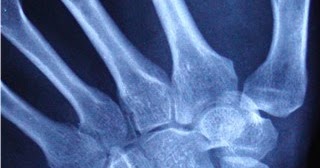

A scaphoid fracture is a break of the scaphoid bone in the wrist. Related online courses on physioplus. Scaphoid is most frequently fractured carpal bone, often occurring after a fall onto an outstretched hand. He or she will ask about the pain. Up to 20% of scaphoid fractures may not be demonstrated on radiographs even with utilization of scaphoid view (occult fractures) (waekerle 1987). It typically occurs in contact and collision sports where an athlete falls on his. The injury pattern for scaphoid fractures is similar to that of adults, with the typical presentation being a fall onto an outstretched hand. Your healthcare provider will examine your hand and wrist, and check for tenderness. Some anatomy around your wrist. Cast immobilization avoids surgical treatment and. There are many different ways one can experience a scaphoid fracture, and the type of. Distal radius fractures programme online course: Their conclusion is that in the case of fractures. An assessment of the stability of the fracture may be more critical to fracture healing than many of the casting variables above, as it is likely that stable undisplaced fractures will heal readily. Return to an office job is possible within the confines of the plaster, however most. How is scaphoid fracture diagnosed and treated. Treatment for scaphoid fractures depends on the type of fracture.